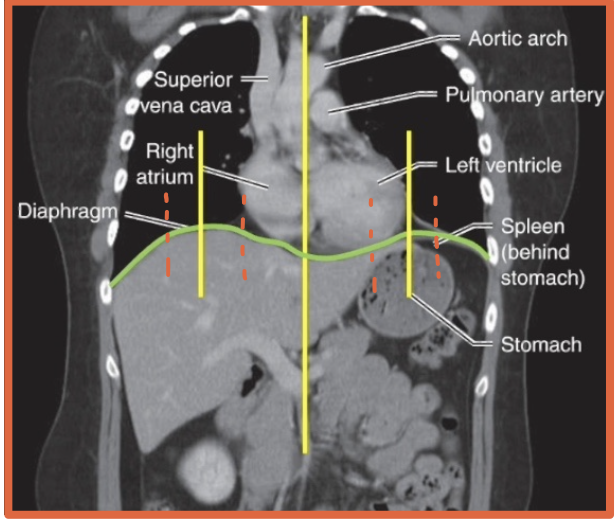

What is the diaphragm?

A thin curved sheet of muscle separating the thoracic and abdominal cavities

What is a hemidiaphragm?

A term used to describe a half of s diaphragm because they often act seperately

Where is the liver located relative to the hemidiaphragms?

Under the right hemidiaphragm

R + Liver = River

Where is the stomach located relative to the hemidiaphragms?

Under the left hemidiaphragm

Stomach took an L